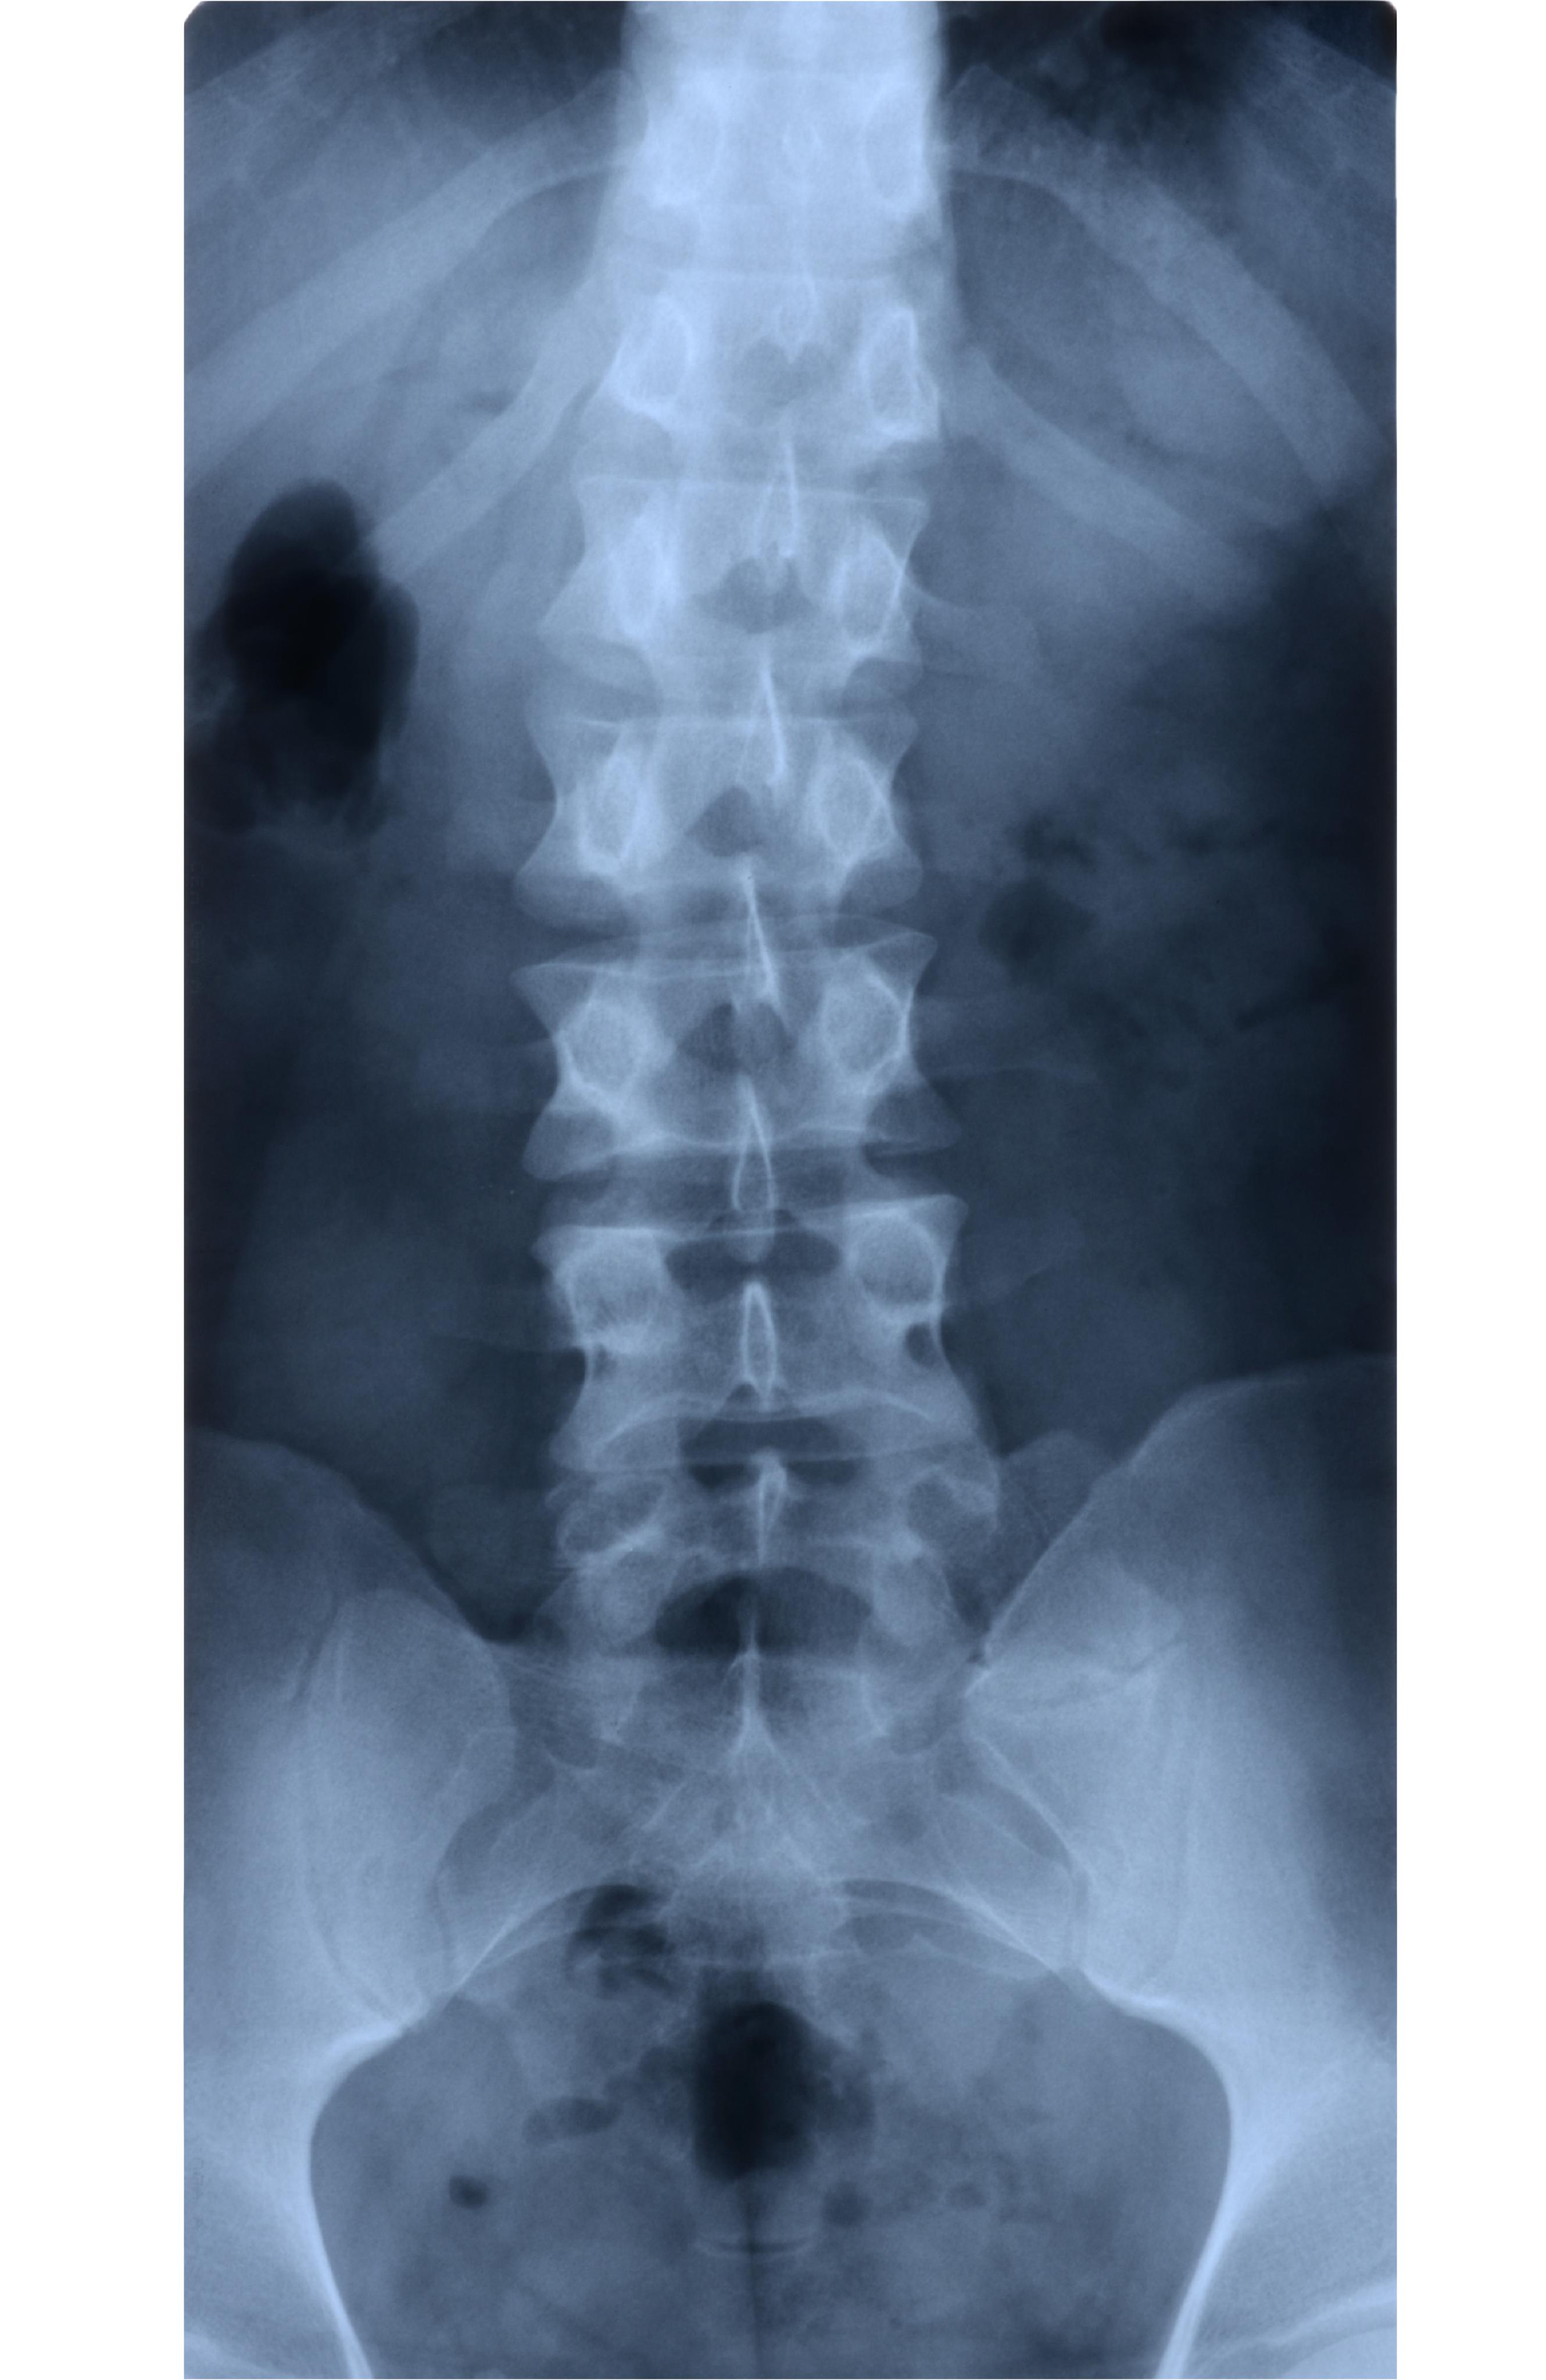

Does Lumbosacral X Ray Include Coccyx . This area includes the lumbar region and the. No patient rotation as demonstrated by superimposition of the. The entire sacrum and coccyx should be visible from l5/s1 to terminal coccyx. Lumbosacral magnetic resonance imaging (mri) studies usually fail to include the coccyx unless a specific request is made for coccygeal visualization. This area includes the lumbar. This area includes the lumbar region and the sacrum, the area that connects the spine to.

X Ray Of The Lumbosacral Spine Normal Perfect Stock P vrogue.co Does Lumbosacral X Ray Include Coccyx The entire sacrum and coccyx should be visible from l5/s1 to terminal coccyx. Lumbosacral magnetic resonance imaging (mri) studies usually fail to include the coccyx unless a specific request is made for coccygeal visualization. No patient rotation as demonstrated by superimposition of the. This area includes the lumbar region and the sacrum, the area that connects the spine to. This. Does Lumbosacral X Ray Include Coccyx.

Xray Image of Lumbosacral (LS) Spine. Stock Image Image of doctor Does Lumbosacral X Ray Include Coccyx The entire sacrum and coccyx should be visible from l5/s1 to terminal coccyx. This area includes the lumbar region and the. This area includes the lumbar. This area includes the lumbar region and the sacrum, the area that connects the spine to. No patient rotation as demonstrated by superimposition of the. Lumbosacral magnetic resonance imaging (mri) studies usually fail to. Does Lumbosacral X Ray Include Coccyx.